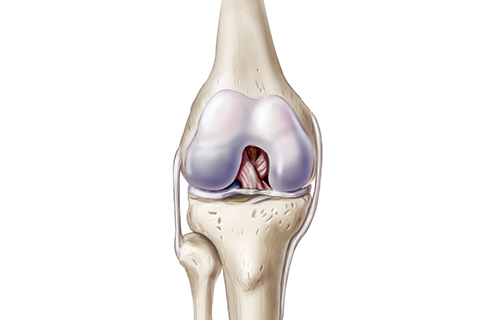

• 십자인대파열

무릎 관절의 안정성을 유지시켜 주는 십자인대가 파열된 질환입니다.

십자인대파열 치료방법

• 비수술적 치료 약물치료, 보조기 착용

• 수술적 치료 전장십자인대 재건술

• 반월상연골판파열

반월상 연골판 파열은 가장 흔한 무릎 부상 중 하나로 신체접촉이 많은 운동선수들에게 발생할 위험이 높은 질환입니다.

반월상연골판파열 치료방법

• 비수술적 치료 약물치료, 물리치료, 주사치료

• 수술적 치료 반월상 연골 절제술, 반월상 연골 봉합술, 반월상 연골 이식술